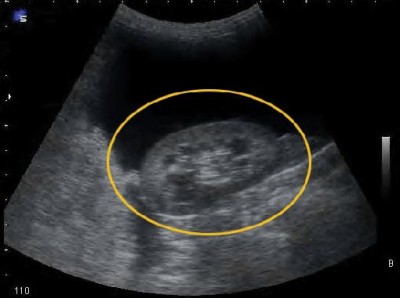

Niercysten zijn ronde met vocht gevulde holten in de nieren. Enkelvoudige cysten zijn niet gevaarlijk en komen na het 50e j aar veel voor. Hoewel zich in een cyste kanker of infectie kan ontwikkelen, zijn dergelijke complicaties zeldzaam. Maar bij polycysteuze nierziekte, een veelvoorkomende erfelijke aandoening, kunnen in de nier talrijke cysten ontstaan, waardoor de nier abnormaal groot wordt en tenslotte nierfalen het gevolg is.

Bij niercysten kunnen zich ook in andere organen cysten ontwikkelen, met name in de lever. Bij sommige kinderen is de ziekte reeds bij de geboorte volledig aanwezig, hetgeen meestal resulteert in een doodgeboorte of overlijden vlak na de geboorte. Bij anderen ontstaat de ziekte vroeg in de jeugd. Maar meestal doen de symptomen zich pas tussen 30 en 40 jaar voor. De complicaties zijn ademhalingsklachten, leverziekte, nierfalen, verhoogde bloeddruk en hartfalen.

niercysten